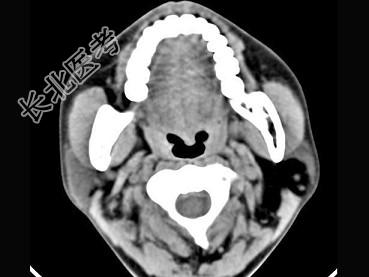

- 多项选择题男,38岁, 左侧腮腺渐进性肿大1年,无压痛, CT扫描如图所示,正确的描述或诊断是 ( )

A、左侧腮腺区见低密度肿块,CT值约为-200Hu

B、肿块边缘清楚,未见邻近结构受侵

C、囊肿

D、脂肪瘤